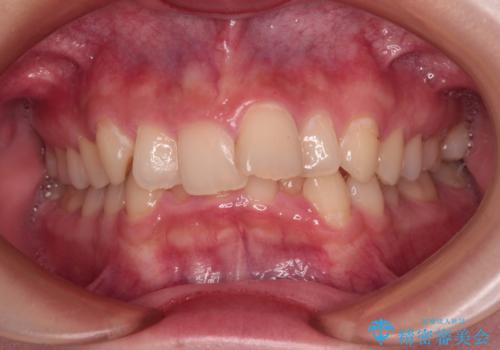

受け口と八重歯を改善 インビザライン矯正治療